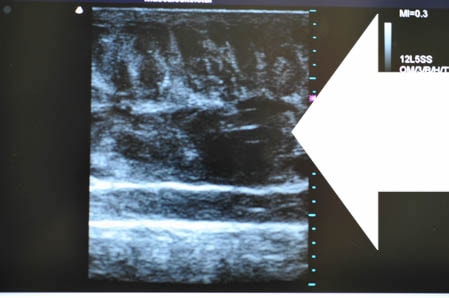

いつものように3Dタッチビュー(超音波)で

皮下脂肪層を評価してみましょう。

左太もも前面。